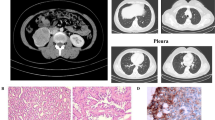

A 15-year old female presented with a large right-sided abdominal mass. Her family history included uterine and cutaneous leiomyomas and a confirmed FH mutation in mother’s family (Fig. 1a). Physical examination revealed small, cutaneous lesions of the lower legs, suggestive for leiomyomas. On MRI using a customized HLRCC-protocol (Table 1), the mass was mostly cystic with peripheral solid nodules (Fig. 1b, c). The nodules showed strong enhancement after contrast administration and restricted diffusion on diffusion-weighted imaging (DWI). In the left kidney, multiple cystic lesions were observed without solid components. Brain MRI and total body FDG-positron emission tomography (FDG-PET) did not reveal signs of metastatic spread. Right-sided nephrectomy revealed an RCC with a maximum diameter of 20 cm (T2N0M0, four lymph nodes sampled), with tumor cells lining the cysts. There was no spread beyond the kidney and resection margins were free of tumor. Solid areas consisted of vital epithelial tumor with a predominantly tubular, partially papillary growth pattern of strongly eosinophilic cells with mild to moderate nuclear atypia (Fig. 1d, e) and diffuse 2SC staining (Fig. 1f). Prominent nucleoli were seen only in rare areas with papillary architecture, without perinucleolar halos. Germline genetic testing by MLPA confirmed the presence of the familial heterozygous deletion of the FH gene (c.(?_1)_(*1_?)del) in the patient and her 18-year old healthy sister, a deletion which has been previously reported in other patients with HLRCC [3, 6, 16,17,18]. The left kidney is monitored with MRI’s at 3 and 6 months after diagnosis, then every 6 months for 3 years, and yearly thereafter. Whereas the kidney appeared unchanged, the patient developed an ovarian lesion (Fig. 1g) after a follow-up of 30 months, at the age of 18, which was successfully resected and histologically characterized as a Leydig cell tumor; a well-demarcated lesion with uniform cells showing large, round nuclei, prominent nucleoli and lack of necrosis, nuclear atypia or mitotic figures. The tumor showed diffuse 2SC staining (Fig. 1h). Whole exome sequencing (Illumina NovaSeq platform) was performed on the Leydig cell tumor, but a second hit in the FH gene was not identified.

Case 1 (female, 15 years, renal cell carcinoma and Leydig cell tumor): a family pedigree; b–c contrast-enhanced T1W-MRI (b) and abdominal T2W-MRI (c) showing large right-sided kidney mass, which is mostly cystic with peripheral solid nodules (boxes). In the left kidney, multiple cystic lesions (arrows) are observed without solid components; d–f histology of the renal tumor: vital epithelial tumor with a predominantly tubular, partially papillary growth pattern (d) of strongly eosinophilic cells with mild to moderate nuclear atypia (e), and diffuse 2SC staining (f). g T2W-MRI of the pelvic region showing a right-sided ovarian lesion (box) with both solid and cystic components. h Ovarian Leydig cell tumor showing diffuse 2SC staining

An 18-year old female, carrier of an FH mutation (c.1330delA; p.Arg444 fs; NM_000143.3), was referred for a suspect lesion in the left kidney, observed on renal MRI surveillance. The mutation was derived from her asymptomatic father and had been previously identified in a distant adult cousin with cutaneous leiomyomas (Fig. 2a). This mutation has not been previously reported. Subsequent CT-imaging with contrast administration showed a 9 mm cystic lesion, with an area of increased density suspect for nodular enhancement (Fig. 2b). A chest X-ray did not reveal signs of lung metastases. A partial nephrectomy was performed; the resected cyst showed focal papillary proliferations with a lining of atypical epithelial cells with some prominent nucleoli. The nucleoli were not significantly enlarged, strongly eosinophilic or surrounded by halos. No necrosis or strong mitotic activity were present. 2SC immunohistochemical staining was positive (Fig. 2c), and the lesion was characterized as an early stage of HLRCC-related RCC. A second hit analysis was not performed. The patient is doing well after a follow-up of 45 months.

Case 2 (female, 18 years, renal cell carcinoma): a family pedigree; data are missing on the presence of leiomyomas in FH mutation carriers; b abdominal CT after contrast administration, showing a 9 mm cystic lesion in the left kidney, with an area of increased density (arrow) suspect for nodular enhancement. c Tumor cells showing diffuse 2SC staining